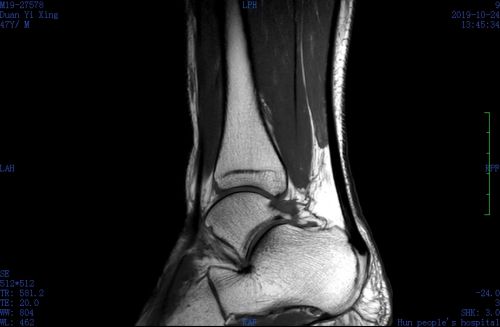

磁共振显示韧带撕裂、跟腱损伤。

同事立即找来轮椅,推着他前往骨科和放射科看病、做检查。急诊磁共振检查显示“左踝外侧副韧带撕裂,距腓后韧带损伤,左踝跟腱损伤,左踝关节周围软组织肿胀”。骨科医生为他进行石膏外固定后,叮嘱他要制动4~6周。